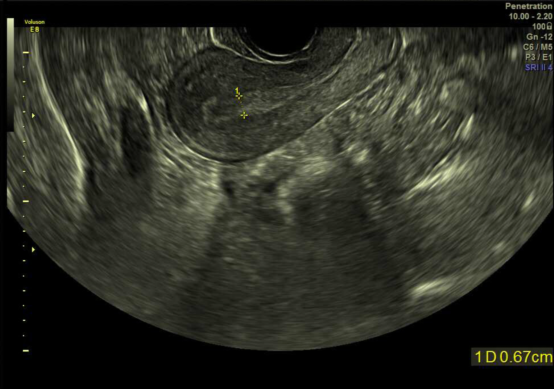

2.2023年8月15日经阴道子宫附件超声:子宫前位,形态饱满,宫腔内探及1.2cm*0.6cm*1.5cm无回声,孕囊旁探及范围约4.0cm*0.6cm*2.2cm的液性暗区,内透声差。双侧附件未见异常回声。

患者LMP:2023.6.23,月经规律,停经30天测HCG310mIU/nl,1天前无明显诱因出现阴道褐色分泌物,量少,无腹痛。2023.08.04行经阴道子宫附件彩超示:宫腔内探及0.7cm*0.8cm*1.0cm无回声,内似见卵黄囊,未见胎芽及原始心管搏动。2023.08.15彩超提示宫腔内探及1.2cm*0.6cm*1.5cm无回声,孕囊旁探及范围约4.0cm*0.6cm*2.2cm的液性暗区。诊断胚胎停育。